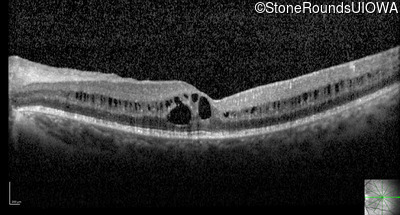

Optical Coherence Tomography - Right - 20/32 -1

Exemplar / OCT Stack